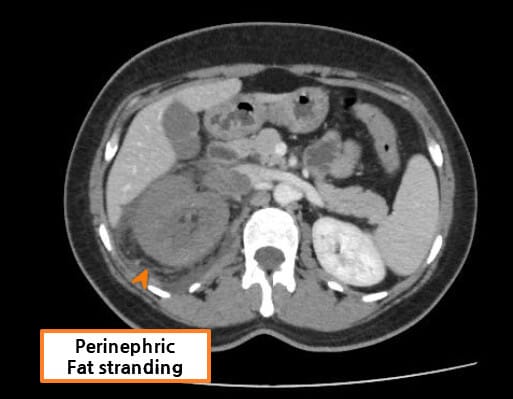

| CT 소견 |

| 🔴 복부 및 사지의 전신 부종 |

| 심한 저알부민혈증으로 인한 복수 및 연조직 부종이 CT에서 관찰될 수 있습니다. |

Abdrabou A, Renal vein thrombosis. Case study, Radiopaedia.org (Accessed on 23 Jul 2025) https://doi.org/10.53347/rID-51291